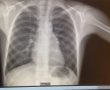

מחקר פורץ דרך בשערי צדק מציע מודל חדשני לזהות סיכונים במטופלים עם דלקת ריאות כבר עם הגעת המטופל לבית החולים

המודל מתמקד בזיהוי רמת הסיכון של דלקת ריאות, ומאפשר להעריך כבר בשלב ההגעה האם מדובר במקרה שמצריך טיפול מיידי או אשפוז, איזה חולים אפשר לשחרר, וסיכון להתדרדרות ומוות במהלך האשפוז